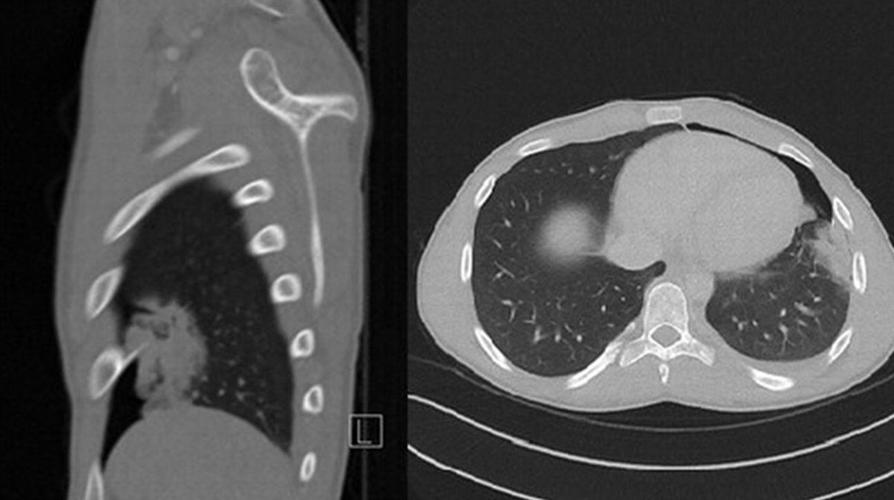

胸部x线片示左侧心尖少量气胸,邻近胸膜粘连.

右侧气胸(肺被压缩约70%) ↓:气带宽度略大于患侧胸廓的1/2,右肺明显

胸 片 正常 左侧胸腔积液 右侧气胸

图15 仰卧位胸片显示深沟征,提示气胸